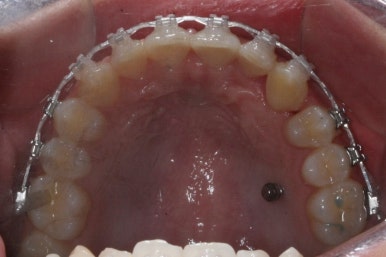

마무리 때의 사진입니다.

윗니만 부분교정하였지만 교합에도 이상 없이 매복되었던 송곳니는 매우 잘 위치를 잡았습니다.

송곳니 부위는 다시 틀어지지 않게 하기 위해 유지철사를 붙여주었습니다.

부산매복치아교정 상악 부분교정을 통해 매복치를 교정해준 이번 치료의 전후사진 비교입니다.

썩은 유치 대신 영구치 송곳니는 매우 자연스럽게 위치되었습니다. 아랫니는 교정하지 않았기 때문에 약간 삐뚠 느낌은 남아있지만 맞물림은 크게 문제가 없게 마무리 되었습니다.